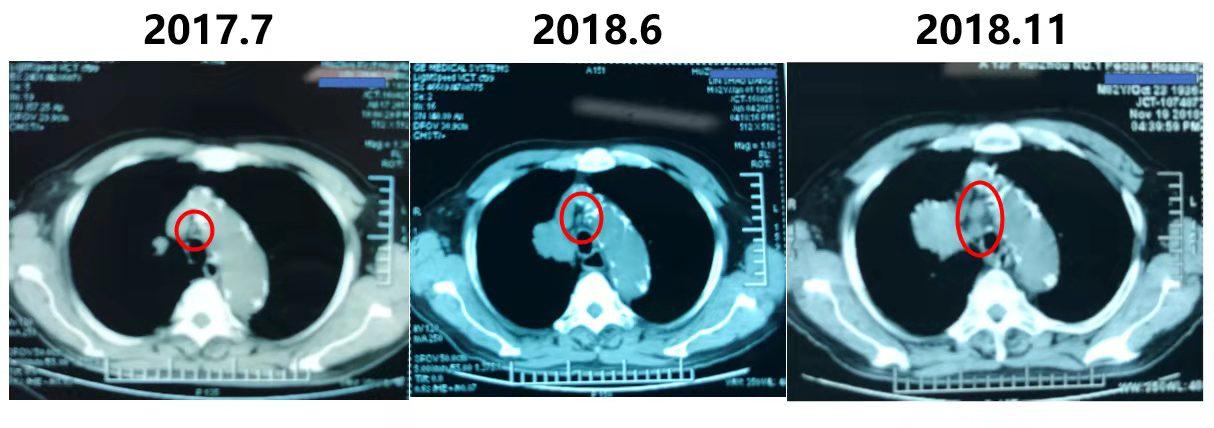

2017.7胸部CT已经看到右上肺的病变了,那时候大小17*15mm。

2018.6复查CT,提示病灶增大,大小为45*34mm。

而到了2018.11复查CT,提示病灶进一步扩大,大小为50*34mm。

2017.7,临床分期 T1bN0M0 IA期

2018.6,临床分期 T2bN0M0 IIA期

2018.11,临床分期 T2bN2M0 IIIA期